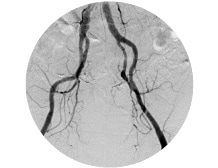

Angiography [OPTION]

High-speed, high-definition, real-time DSA is avaliable at 7.5 fps on a 1024 X 1024 matrix.